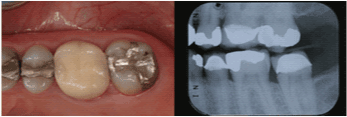

| Maxillary Left Second

Molar |

7 |

53.7% |

|